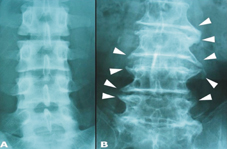

左圖為年輕的脊椎,沒有骨刺;右圖為年老退化的脊椎,雖可見明顯的骨刺,但老人家行動自如。